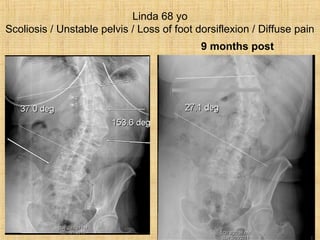

Linda 68 yo

Scoliosis / Unstable pelvis / Loss of foot dorsiflexion / Diffuse pain

9 months post

Linda 68 yo Scoliosis/ Unstable pelvis / Loss of foot dorsiflexion / Diffuse pain 9 months post

Scoliosis Patients Are Missinglateral Lordotic Curves…“Linda”